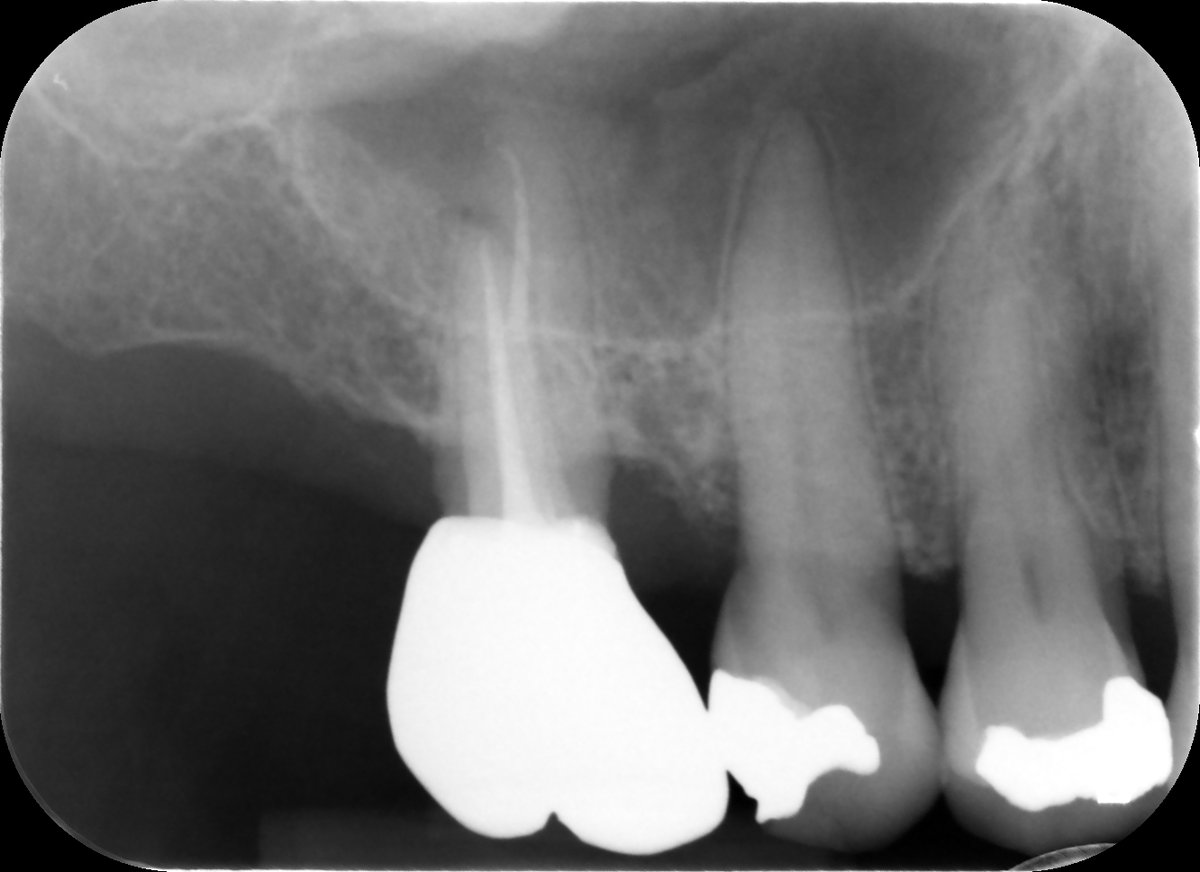

Intentional replantation can be a predictable and viable treatment option. In this case a long LR7 not suitable for root end surgery. No cracks visible under the microscope, MTA root end filling. First radiographic review in 1 month.🙃